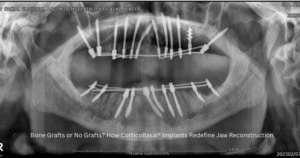

When comparing All-on-4 or All-on-6 implant systems with CorticoBasal® Implants, it becomes evident that the latter offers a more stable,